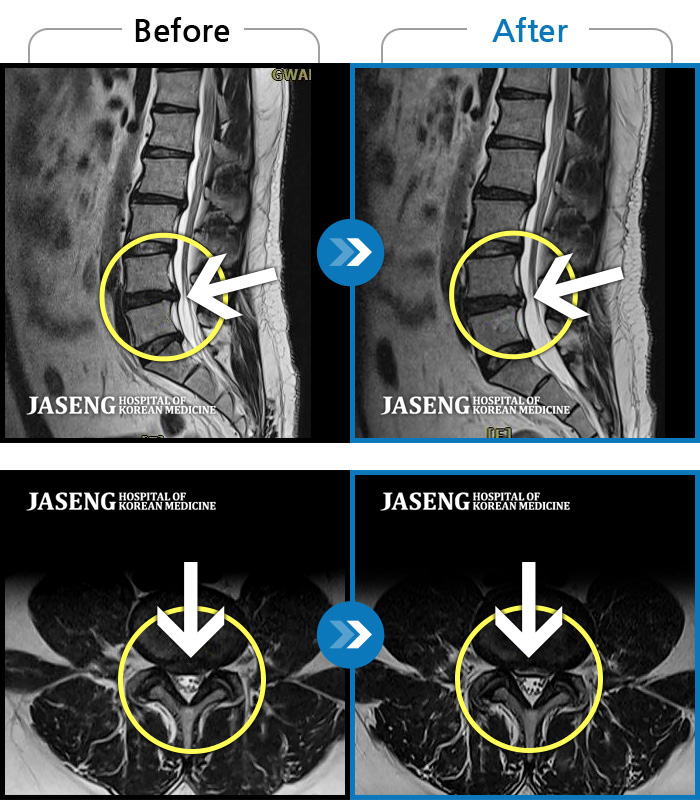

Before

After

허리 통증과 우측 허벅지 통증 및 저림 증상 지속되어 내원하셨습니다.

2022.08.20 ~ 2024.11.08